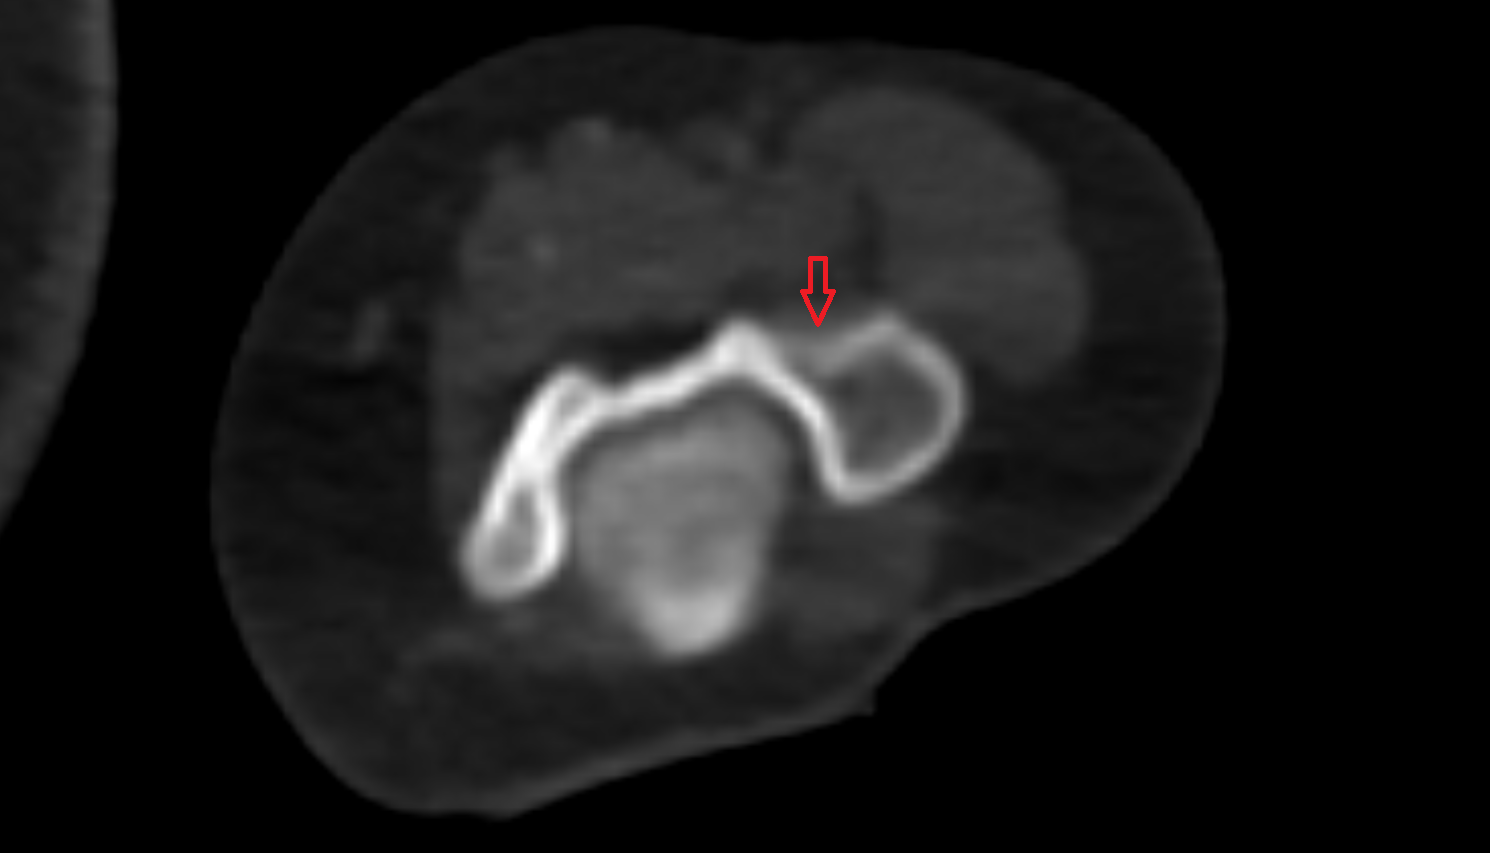

- Knee Joint